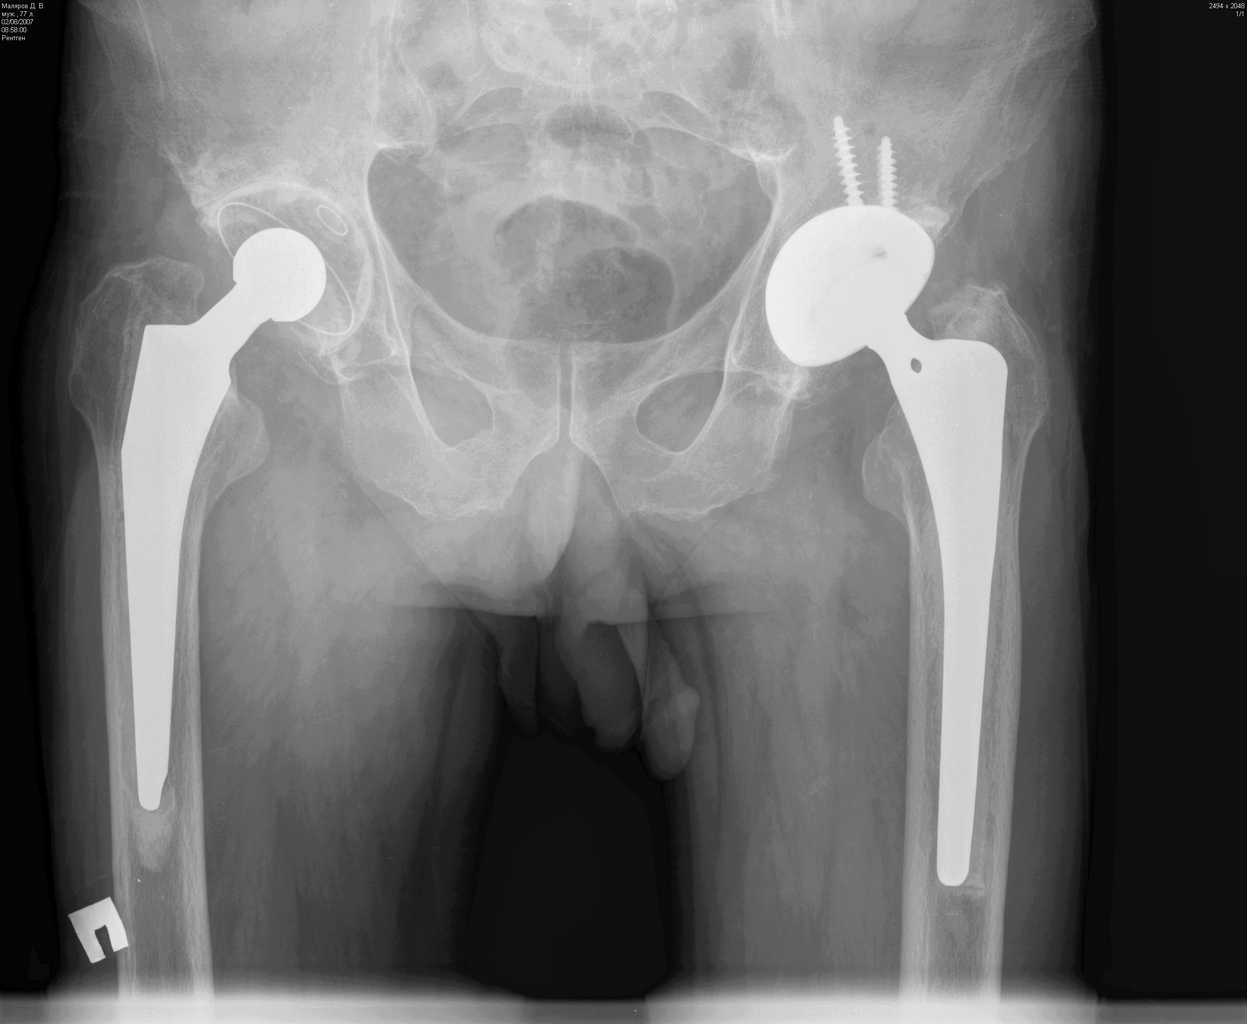

Больной М.,75л. Страдает коксартрозом. В 2005 справа и в 2007 г. слева эндопротезирование т\б суставов.

На мой взгляд, оба бедренных компонента нестабильны, это и является причиной боли. Оба компонента явно меньше требуемого размера. Ножка Мюллера показывает отличные результаты, но только при формировании рассеченной цементной мантии.

Евгений, справа ножка нестабильна, возможно она уже развернулась в мантии, да и вокруг чашки есть просветления. Видимо надо планировать повторное вмешательство с удалением ножки и цемента. Ножка должна удалиться легко, цемент в значительной своей части тоже. Сменить ножку лучше на бесцементную и не обязательно ревизионную, пойдет любая с элементами диафизарной фиксации. Состояние впадины оцените во время операции.

Признаки нестабильности ножки заметные, выраженная демаркация зоны кость - цемент. Нестабильность чашки сомнительная. Согласен, не обязательно применение ревизионной ножки, но фиксацию предпочел бы цементную. Данный метод фиксации уменьшает риск интраоперационного перелома бедра, упрощает и ускоряет период реабилитации пациентов пожилого возраста. Вероятно, желательно применить другой тип ножки, я бы использовал CS (CSL) -PLUS Plus Orthopedics, т.с."бюджетный" вариант. Может возникнуть проблема с удалением цементной "пробки".

Уважаемый Евгений, понятие стресс шилдинга не является синонимом нестабильности, хотя и является признаком неадекватности распределения нагрузки в системе "имплантат - кость" и может в последствие привести к "расшатыванию" эндопротеза.В данном случае на рентгенограмме правого тазобедренного сустава отчетливо видна сформированная "замыкательная пластинка" на внутреней поверхности кости (на границе с цементом). Причем, как раз в проксимальном отделе сегмента, то есть в зоне определяющей стабильность имплантатов типа Мюллер.

Болевой синдром в тазобедренном суставе при осевой нагрузке не характерен для корешкового с-ма или ишалгии. В данном случае, скорее всего мы наблюдаем "обратный" "с-м поршня". Когда изменение давления в костномозговом канале за счет перемещения нестабильной ножки (поршня)передается не в дистальные отделы бедра (классический "с-м поршня"), а за счет неподвижной (или малоподвижной) цементной пробки "отражается" в проксимальную часть, где и возникает боль. Возможно, конечно и наложение неврологическои и ортопедической симптоматики. Но, на мой взгляд, данные рентгенограммы дают достаточно информации о наличие проблем, по крайней мере, со стороны ножки эндопротеза правого тазобедренного сустава. А R-граммы, действительно хорошие... по качеству.

На мой взгляд имеет место нестабильность обоих бедренных компонентов. Боль, которая имеет место у больного характерна при проблемах в области тазобедренного сустава. Нужно рассматривать вопрос о ревизионном эндопротезировании, в частности бедренного компонента.